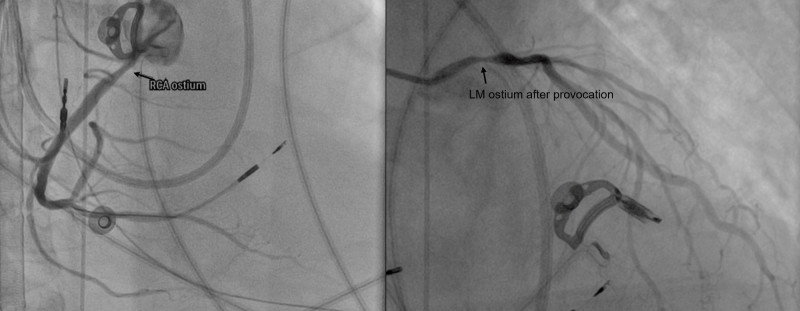

他指出,臨床觀察顯示,冠狀動脈痙攣多與多重因素相關,包括高血壓、高血脂、糖尿病等三高族群風險較高,同時也與自律神經失衡有關,特別是交感神經過度活化,容易造成血管異常收縮,部分病人在發作前可能出現胸悶、胸痛、心悸或冒冷汗等症狀,也有病人如洪先生一般,一旦發作馬上併發嚴重心律不整直接導致猝死,因此臨床上需透過病史、心電圖變化、冠狀動脈攝影或心導管進行誘發測試等檢查綜合判斷,及早發現並介入治療,才能降低致命風險。